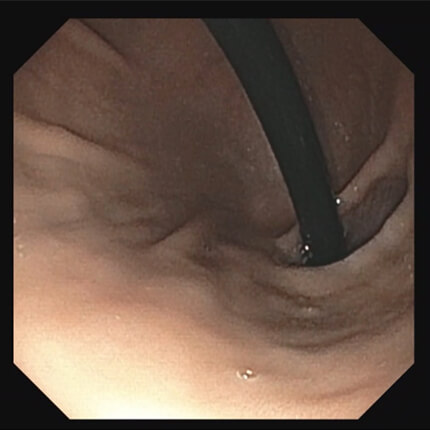

必要に応じて生検

消化管粘膜の一部を採取し、病理検査を行います。